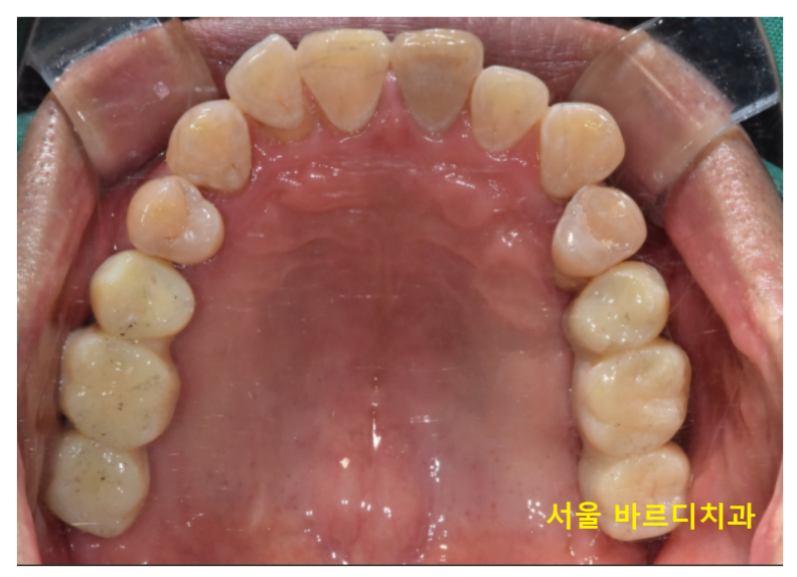

오늘 소개해드릴 환자분

하루 2갑씩 피는 환자분이셨습니다.

환자분을 처음 뵈었을 때

솔직히 말씀드려 안 흔들리는 치아가 없었습니다.

잇몸이 많이 망가졌어요.

윗니는 개수로만 4개 없음

아랫니는 2개 없음

이건 이미 뽑힌 상태만 세었을 때이고

뽑을 치아도 상당했습니다.

길동 치과 완성 후 사진입니다.